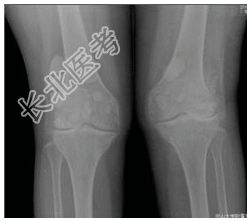

- [材料题] 患者女,55岁,双膝隐痛十余年。查体:双膝压痛,局部软组织肿胀,触之硬物感。行双膝关节正侧位片检查。

- 简答题1、患者的诊断及依据是什么?

- 简答题2、鉴别诊断是什么?